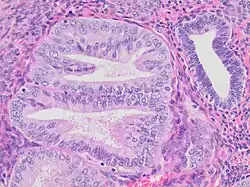

Endometrial intraepithelial neoplasia

- Architectural gland crowding

- Altered cytology relative to background glands

- Minimum size of 1 mm

- Exclusion of adenocarcinoma

- Exclusion of mimics

Mitoses should also preferably be seen. Compare to normal endometrial gland at right.